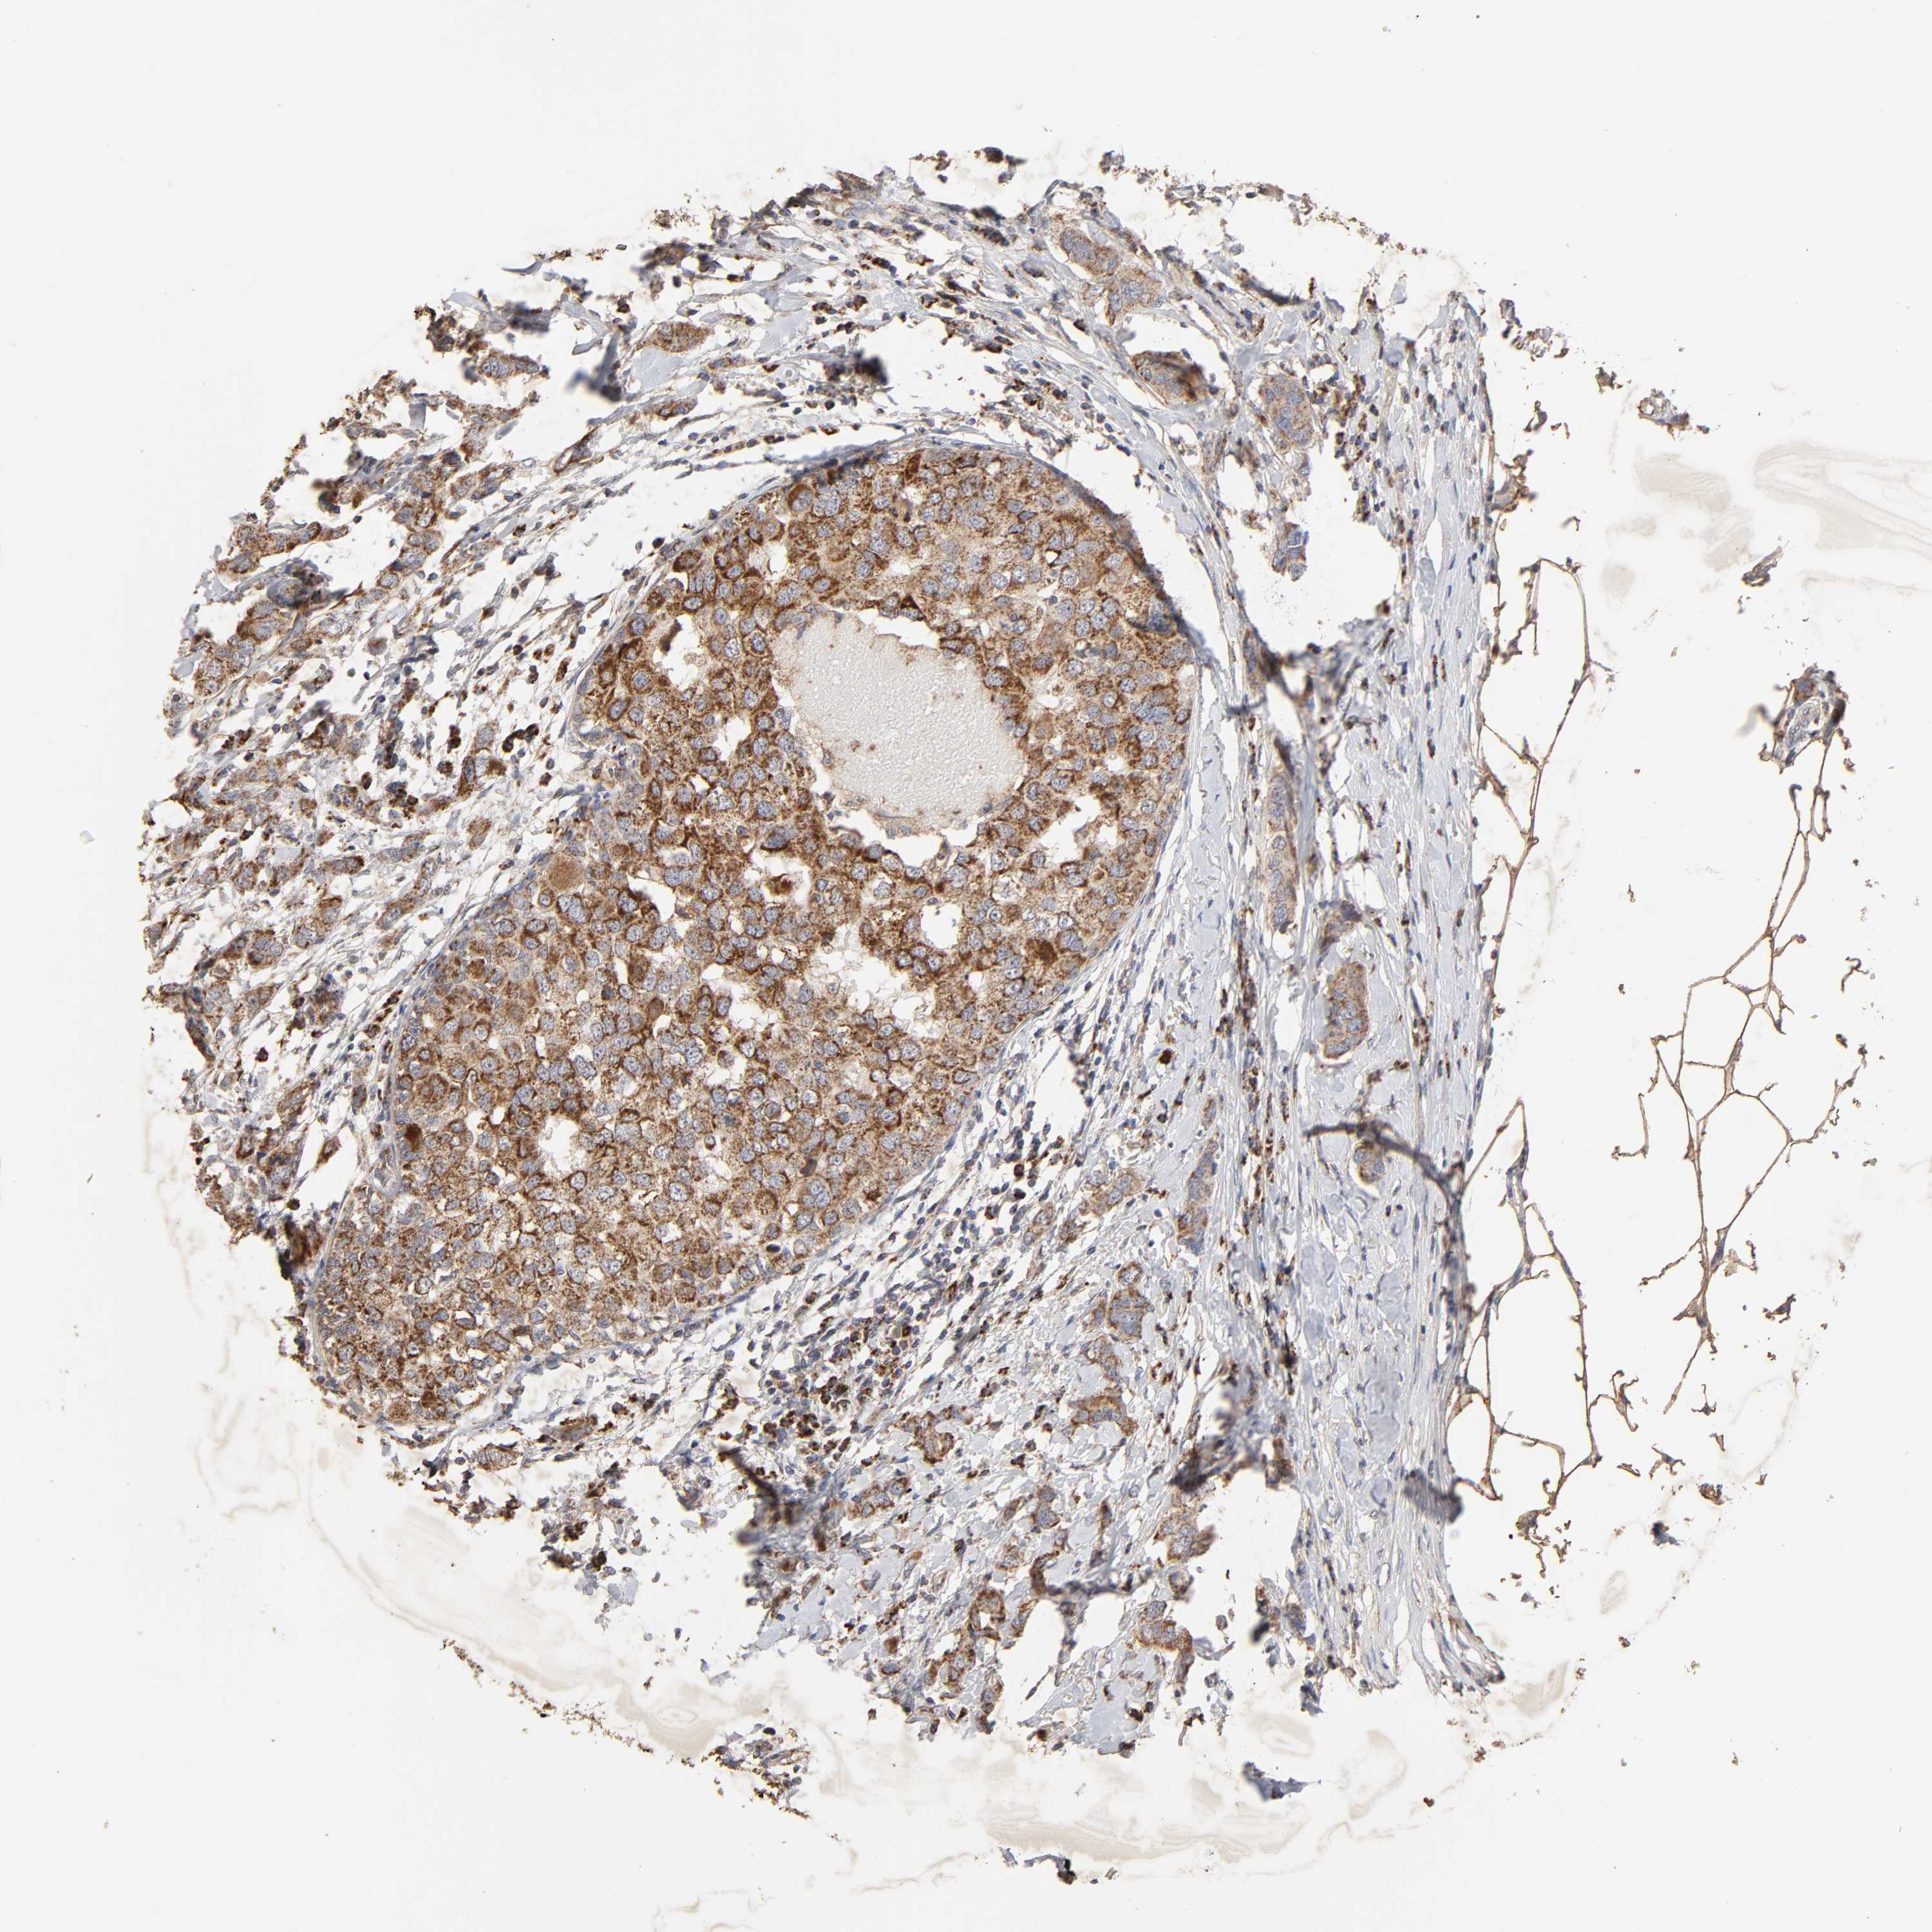

CANCER BREAST CANCER Show tissue menu

BRCA TCGA BRCA VALIDATION PROTEIN EXPRESSION

ANTIBODIES

AND

VALIDATION